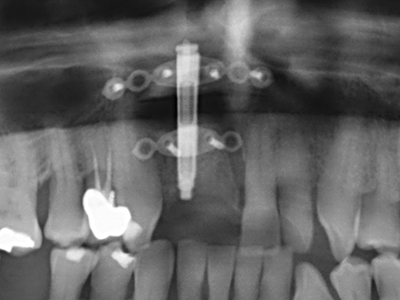

Il tessuto osseo non è semplicemente una struttura minerale, ma contiene anche una percentuale significativa di fibre di collagene. Ciò significa che non possiede solo una buona forza di compressione, ma anche un certo livello di flessibilità che è possibile sfruttare durante l'esecuzione degli accrescimenti di osso. Nella procedura di espansione classica con incisione ossea, la cresta alveolare atrofizzata viene incisa longitudinalmente ed espansa con cautela dopo aver raggiunto una profondità di osteotomia adeguata (figg. 13-16), idealmente senza una sostanziale rimozione del periostio (Brugnami, Caiazzo et al. 2014, Stricker, Fleiner et al. 2014). I sistemi a piastra e vite con distanza di espansione incrementale si sono dimostrati efficaci nella separazione delle due lamelle ossee restando al di sotto della soglia di frattura. In generale, sono richieste larghezze dell'osso residuo di almeno 3-4 mm (Chiapasco, Zaniboni et al. 2006) per garantire un'adeguata flessibilità e una copertura sufficiente dell'osso per gli impianti futuri. Se necessario, un'osteotomia di rilascio verticale su uno o più lati può migliorare la flessibilità. Una combinazione con ulteriori tecniche di accrescimento, in particolare dal lato buccale, è stata descritta come un'alternativa alla tecnica classica.

La procedura di incisione è particolarmente atraumatica e non comporta una perdita significativa di dimensione durante l'utilizzo delle seghe piezoelettriche, così come non si notano differenze rilevanti tra impianti in mandibole incise e impianti in una cresta alveolare senza deficit osseo (Chiapasco, Zaniboni et al. 2006, Danza, Guidi et al. 2009). Una sufficiente irrigazione continua è essenziale, tuttavia, in particolare con incisione profonda e localmente ristretta, per prevenire la sollecitazione termica nelle regioni apicali dell'osteotomia.